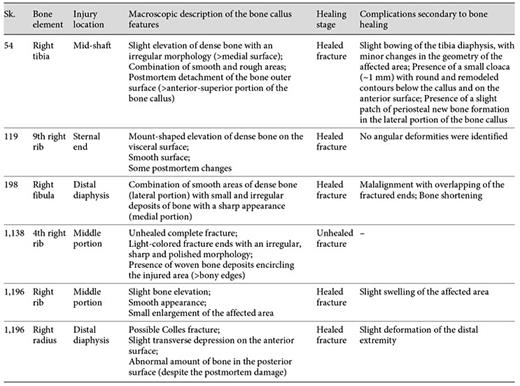

Histomorphology of the Bone Callus

The histological analysis of the 6 bone samples showed a well-preserved bone microanatomy with good bone birefringence. Some structural differences were found when the bone calluses were compared (table 4).

Evaluation of the histological features of the bone callus by individual, sample, healing stage, and type of trauma diagnosis

Of the 5 bone samples with an apparently healed callus, only 2 (Sk. 54 and 1,196 - rib sample) presented a truly mature and remodeled microstructure. For example, in the lateral portion of the Sk. 54 right tibia callus, a haphazard arrangement of Haversian systems, interstitial lamellae, and enlarged osteon canals crisscrossed by Volkmann's canals was observed. Discontinuous rows of intracortical lamellae, which resemble ‘Grenzstreifen' [35,36,37] were seen separating the inner cortical bone from the secondary compact bone. At some points, erratic resorption lacunae, or sinuous lacunae [37], parallel to the intracortical lamellae were also noticed. In the medial portion of the bone callus, a profusion of randomly organized lamellae in different stages of maturation was observed. In this area, a more chaotic structure formed by osteons, Howship's lacunae and remnants of densely packed lamellae were seen. The periosteal microarchitecture ranged from a thin rim of bone to a denser and/or ruffled surface showing, at some points, irregular resorption spaces (fig. 6a-e).

a Microscopic view of the Sk. 54 right tibia sample showing the cortical tissue formed by osteons (white arrowheads) intersected, at some points by Volkmann's canals (black arrowheads). The periosteal surface was composed of a thin rim of bone (white asterisks). b Segment formed by osteons, intracortical lamellae (circle 1), and resorption spaces (circle 2). b1 Detail of the intracortical lamellae (or ‘Grenzstreifen'; black arrowheads) separating rows of osteons (white arrowheads). b2 Another magnification showing some resorption lacunae (or sinuous lacunae; white asterisk) in the intracortical lamellae (black arrowheads) and at the periosteal surface (white asterisk). Note the presence of osteons with enlarged Haversian canal (white arrowhead). c Segment showing a haphazard cortical microstructure formed by osteons (white arrowheads), interstitial lamellae (white asterisks), and compact intracortical lamellae (black arrowheads). d Thick layer of dense bone at the periosteal surface (black asterisks) connecting the cortical tissue formed by different sized osteons (white arrowheads). e Another segment revealing erratic osteons (white arrowheads) surrounded by elongated intracortical lamellae (black arrowheads). Polarized light. Magnification ×40; ×100.

a Microscopic view of the Sk. 54 right tibia sample showing the cortical tissue formed by osteons (white arrowheads) intersected, at some points by Volkmann's canals (black arrowheads). The periosteal surface was composed of a thin rim of bone (white asterisks). b Segment formed by osteons, intracortical lamellae (circle 1), and resorption spaces (circle 2). b1 Detail of the intracortical lamellae (or ‘Grenzstreifen'; black arrowheads) separating rows of osteons (white arrowheads). b2 Another magnification showing some resorption lacunae (or sinuous lacunae; white asterisk) in the intracortical lamellae (black arrowheads) and at the periosteal surface (white asterisk). Note the presence of osteons with enlarged Haversian canal (white arrowhead). c Segment showing a haphazard cortical microstructure formed by osteons (white arrowheads), interstitial lamellae (white asterisks), and compact intracortical lamellae (black arrowheads). d Thick layer of dense bone at the periosteal surface (black asterisks) connecting the cortical tissue formed by different sized osteons (white arrowheads). e Another segment revealing erratic osteons (white arrowheads) surrounded by elongated intracortical lamellae (black arrowheads). Polarized light. Magnification ×40; ×100.

In contrast with the aforementioned case, the histomorphology of the Sk. 54 bone callus is compatible with a mature and remodeled fracture. The presence of a cloaca and the observation of small patches of intracortical lamellae or ‘Grenzstreifen' confirm that this individual had developed a posttraumatic osteomyelitis. Albeit more common in specific infections characterized by slowly growing new bone formation (treponematoses) [35,36,37,61], ‘Grenzstreifen' may also occur in cases of nonspecific osteomyelitis [37]. In the case under discussion, the ‘Grenzstreifen' separates the original cortical bone affected by trauma from a secondary inflammatory process imposed by osteomyelitis.